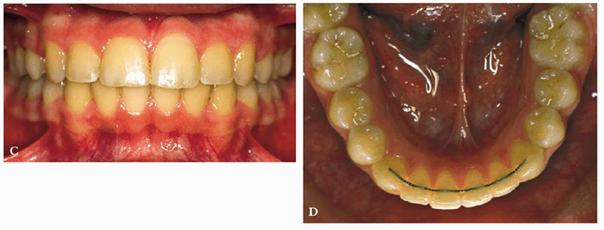

RESULT: The patient underwent an early orthodontic treatment for 1 year

that achieved arch balance, improvement of esthetics, and health of the oral

tissues. Furthermore, the improved smile contributed to greater self-confidence

and an improved sense of well-being (Figures 27-9C and D).

Figure 27-9C and D: The patient's smile and the lower arch after the orthodontic treatment: good balance and esthetics are achieved.